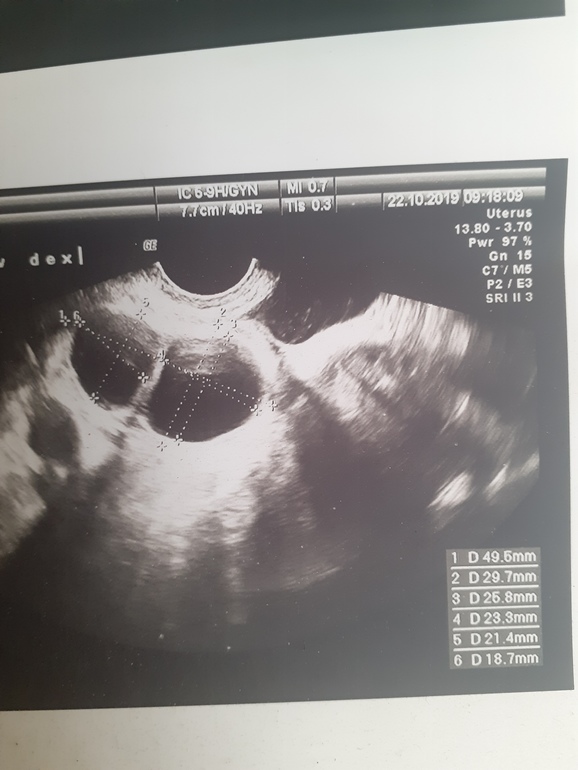

Вот смотри какие размеры. Лопнули они на следующий день после этого узи. Кажется, это был 24 дц